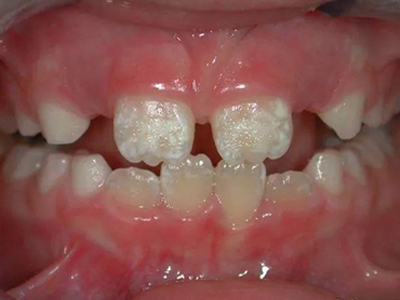

牙釉质发育不全牙齿白斑图

牙釉质发育不全患者可以仅仅出现牙齿色泽和透明度的改变,形成白垩色釉质,即类似于牙齿上有白斑,此时牙冠形态通常较完整。